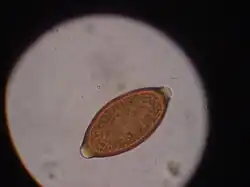

Trichuris vulpis is a whipworm that lives in the large intestine of canines in its adult stages. Out of different types of worms, Trichuris vulpis is one of the smaller worms with a size ranging from 30–50 mm in length. As the name suggests, the worm has a whip-like shape with distinct features including a small, narrow anterior head, which is the digestive part of the worm, and a larger posterior tail, which is the reproductive part of the worm. Eggs from T. vulpis are oval shaped with bipolar plugs and contain a thick outer shell. Their sizes range from 72–90 μm in length and 32–40 μm in width.[1] Because of their thick outer shell, T. vulpis eggs are very resistant to environmental extremes such as freezing or hot temperatures, thus allowing for their long viability in the outside world.[2]

Egg of T. vulpis

The life cycle of Trichuris vulpis begins with the adult whipworms living in the large intestines of dogs. T. vulpis lay many eggs in the large intestine and are released in the feces into the outside environment. When eggs are released into the outside environment, these unembryonated eggs are able to form embryos in the soil in about 2–4 weeks, at which point they become infective when ingested by the new host. An infective larva develops within the egg before it is even ingested by the new host.[3]

Infection of this parasite can be confirmed with detection of eggs in the canine's feces. Adult T. vulpis females can produce more than 2,000 eggs per day. These eggs can be detected in the canine's feces by the fecal flotation method.[14] This method utilizes the differences of specific gravity of eggs, fecal debris, and the flotation solution.[15] Although these eggs are dense, the use of proper fecal flotation technique using a sugar solution and centrifugation can increase the chances of identifying these eggs in a fecal sample.[16] Multiple fecal samples may need to be tested as the eggs may be shed periodically.[17]